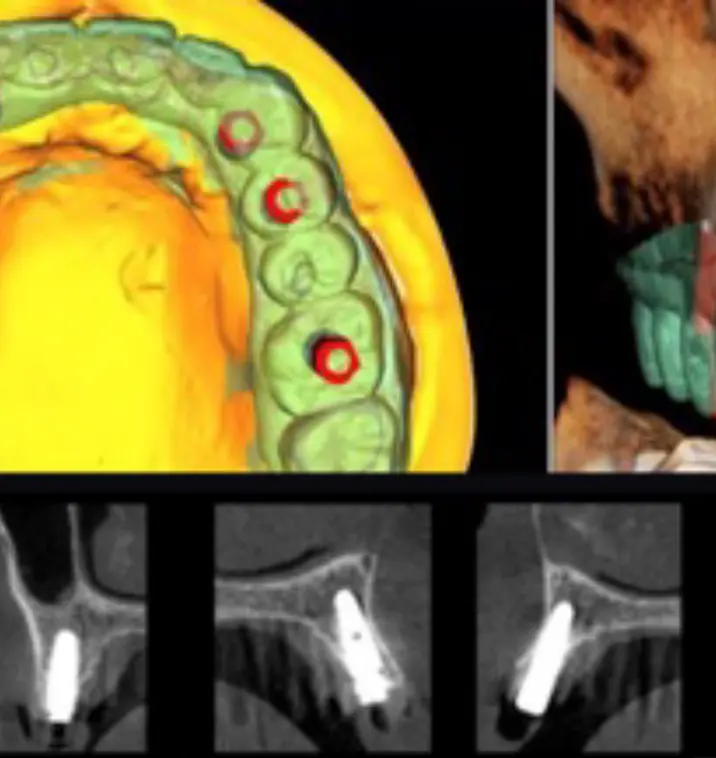

そもそも私たちが20年以上も前から追求してきたこと、それは、インプラント治療を短期間で終わらせること(short)、安全に行うこと(safety)、小さな切開で治療すること(small)、簡単な術式を実現すること(simple)。抜歯即時インプラント埋入は、これを叶える術式として、理に適う治療法だったのです。

このように私たちは、「4S」、すなわちshort、safety、small、simpleをすべての治療の起点とし、他の術式を併用・応用するどのような治療であっても、抜歯即時インプラント埋入と同様、常に「4S」を起点とする治療計画を考えています。

当院が提供するインプラント治療は、シンプルかつ最小限の処置で、患者さまの体の負担をできる限り低減するインプラント治療。最近でさえ耳にする機会が多くなった、手術したその日に噛める抜歯即時インプラント治療は、当院では2000年代初めから既に定番となっています。それどころか、昨今の当院では、骨が足りない患者さまでさえ、骨を増やすことなく、ごくシンプルな手術だけで治療するケースが大半です。